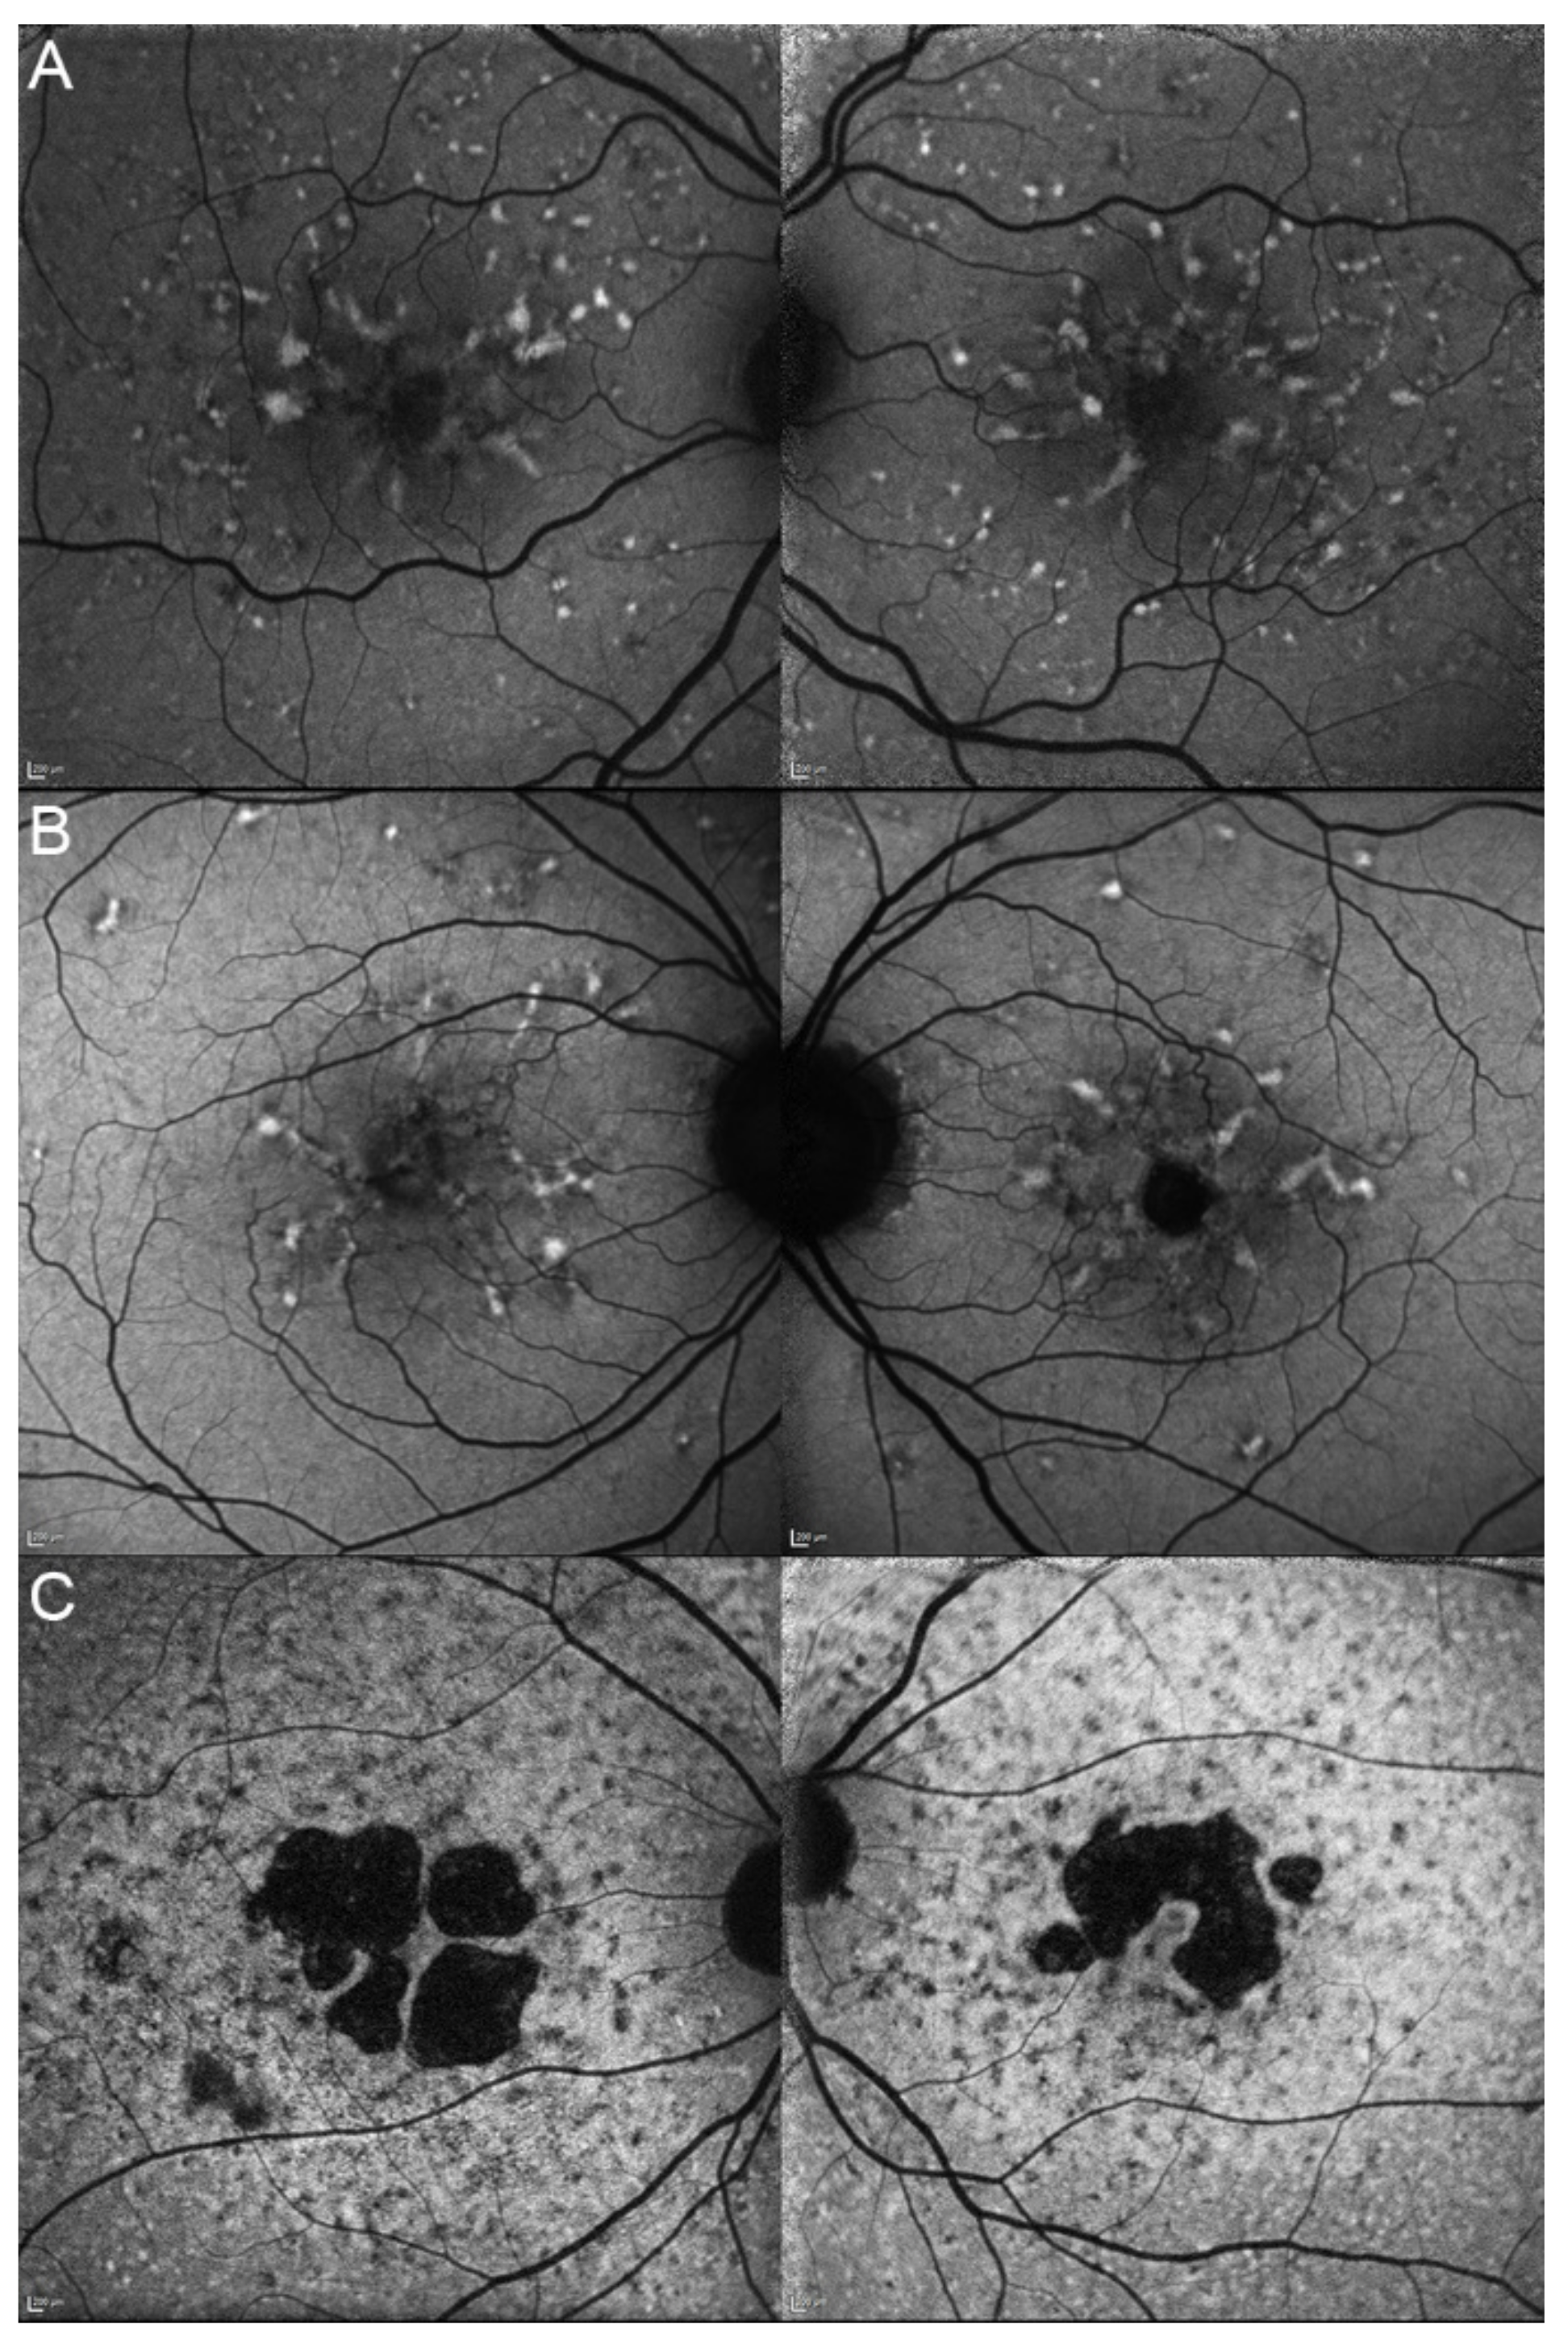

| 13, II.1 | ELOVL4 | 46 | F | Multifocal areolar parafoveal HOAF; mottled pattern of HPAF and HOAF flecks; perimacular to mid-peripheral HPAF flecks | Perimacular EZ loss; perimacular ONL atrophy; subretinal hyperreflective deposits |

| 13, III.2 | ELOVL4 | 19 | F | No special features | Subfoveal hyperreflective deposits (OD) |

| 13, I.1 | ELOVL4 | 82 | M | Areolar HOAF; paracentral mottled pattern of HPAF and HOAF flecks | ONL thinning; perimacular localised EZ loss (OS) |

| 14, II.4 | ELOVL4 | 48 | M | Central mottled pattern of HPAF and HOAF flecks | Central EZ loss; central ONL atrophy; perimacular subretinal hyperreflective deposits |

| 15, II.3 | ELOVL4 | 34 | M | Subfoveal HOAF; concentric ring of HPAF | Central EZ disruption with gap; central ONL atrophy |